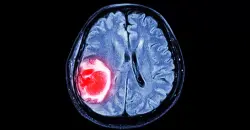

شفق نيوز/ كشف باحثون عن أداء جديدة تعتمد الذكاء الاصطناعي، بمقدورها تحديد الأورام السرطانية بدقة، وتسريع عملية تشخيص المرض.

ويمكن لأداة الذكاء الاصطناعي "الخوارزمية"، التي صممها خبراء في مؤسسة "رويال مارسدن"، ومعهد أبحاث السرطان في لندن، وإمبريال كوليدج لندن، تحديد ما إذا كانت الأورام غير الطبيعية الظاهرة في التصوير المقطعي سرطانية.

ويمكن لهذه التقنية استخراج معلومات مهمة من صور الأشعة التي لا يسهل على العين البشرية رصدها.

واختبر النموذج الذي طوره العلماء لتحديد ما إذا كان بإمكانه تحديد العقد السرطانية بدقة.

وأظهرت النتائج أن نموذج الذكاء الاصطناعي يمكنه تحديد خطر الإصابة بالسرطان لكل عقدة مع قيمة AUC تبلغ 0.87.